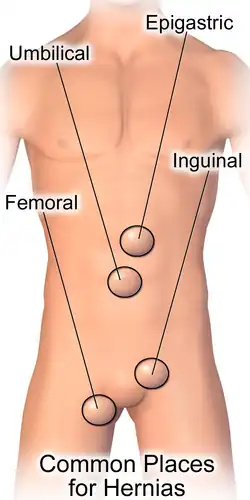

Various types of hernias can occur,[6] most commonly involving the abdomen, and specifically the groin.[6] Groin hernias are most commonly inguinal hernias but may also be femoral hernias.[1] Other types of hernias include hiatus, incisional, and umbilical hernias.[6] Symptoms are present in about 66% of people with groin hernias.[1] This may include pain or discomfort in the lower abdomen, especially with coughing, exercise, or urinating or defecating.[1] Often, it gets worse throughout the day and improves when lying down.[1] A bulge may appear at the site of hernia, that becomes larger when bending down.[1]

Inguinal

By far the most common hernias (up to 75% of all abdominal hernias) are inguinal hernias, which are further divided into the more common indirect inguinal hernia (2/3, depicted here), in which the inguinal canal is entered via a congenital weakness at its entrance (the internal inguinal ring), and the direct inguinal hernia type (1/3), where the hernia contents push through a weak spot in the back wall of the inguinal canal. An indirect inguinal hernia and a direct inguinal hernia can be distinguished by their positioning in relation to the inferior epigastric vessels. An indirect hernia is situated laterally to these vessels, whereas a direct hernia is positioned medially to them. Inguinal hernias are the most common type of hernia in both men and women. In some selected cases, they may require surgery.

Femoral

Femoral hernias occur just below the inguinal ligament, when abdominal contents pass into the weak area at the posterior wall of the femoral canal. They can be hard to distinguish from the inguinal type (especially when ascending cephalad): however, they generally appear more rounded, and, in contrast to inguinal hernias, there is a strong female preponderance in femoral hernias. The incidence of strangulation in femoral hernias is high. Repair techniques are similar for femoral and inguinal hernia.

Umbilical

They involve protrusion of intra-abdominal contents through a weakness at the site of passage of the umbilical cord through the abdominal wall. Umbilical hernias in adults are largely acquired, and are more frequent in obese or pregnant women. Abnormal decussation of fibers at the linea alba may be a contributing factor.

Incisional

An incisional hernia occurs when the defect is the result of an incompletely healed surgical wound. When these occur in median laparotomy incisions in the linea alba, they are termed ventral hernias. These occur in about 13% of people at 2 years following surgery.[27]